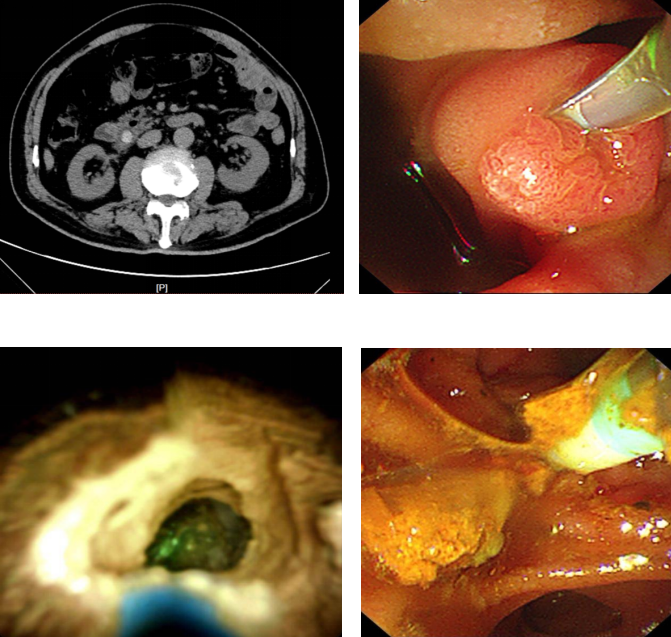

近日,75岁的马先生(化姓)因饮酒后突发剧烈呕吐,检查发现胆总管结石堵塞引发急性化脓性胆管炎,同时合并胰腺炎,病情危急。东南大学附属中大医院消化内科主任冯亚东主任医师团队紧急实施微创手术,运用该院在江苏省内率先开展的数字胆道镜辅助无射线内镜逆行胰胆管造影术(ERCP)治疗胆管结石,通过十二指肠镜,借助先进的胆道子镜系统精确定位结石,采用钬激光将结石粉碎取出,并植入支架疏通胆道。术后第二天马先生即可进食,五天后顺利康复。“从发病开始痛苦万分,到深夜急诊,以及迅速精细的微创手术,中大医院消化内科的医生护士们用专业和温暖创造了生命奇迹!”出院时,患者和家属无比激动地对医护人员说。

中大医院消化内科开展的这项先进的微创ERCP技术为何能让身处危情中的胆管结石患者得到快速的治疗和康复?据介绍,冯亚东主任医师团队最早于2019年在江苏省内率先开展了新型胆道镜直视下无射线ERCP微创手术,这种数字胆道镜的应用,可有效弥补传统ERCP的不足,其中单人经口胆道镜系统的运用较为成熟,其拥有双通道操作系统及高质量成像技术,可直接观察、定位和治疗胆管结石,同时可联合液电碎石和激光碎石等碎石技术治疗困难结石,为胆管结石的诊疗提供了新手段。